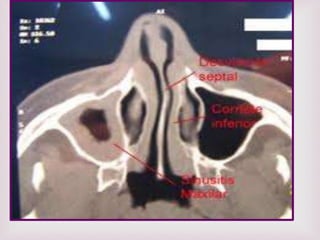

EXÁMENES RADIOGRÁFICO

RX SENOS PARANASALES

De poca ayuda en el dx de pólipos

nasales altos falsos positivos y falsos

negativos.

TUMOGRAFIA COMPUTADA TC

Para confirmar localización y

extensión de la lesión. De gran

utilidad permite planear tipo de

cirugía y evitar complicaciones .

RMN.

Se usa para diferenciar pólipos de:

-Tumores

-Mucoceles

-Infección fúngica

DIAGNOSTICO DIFERENCIAL

 Neoplasia maligna

 Rinitis vasomotora

 Rinitis alérgica sinusitis crónica

 Desviación septal

 Hipertrofia de cornete

 Quiste nasoalveolar

 Nasoangiofibroma.